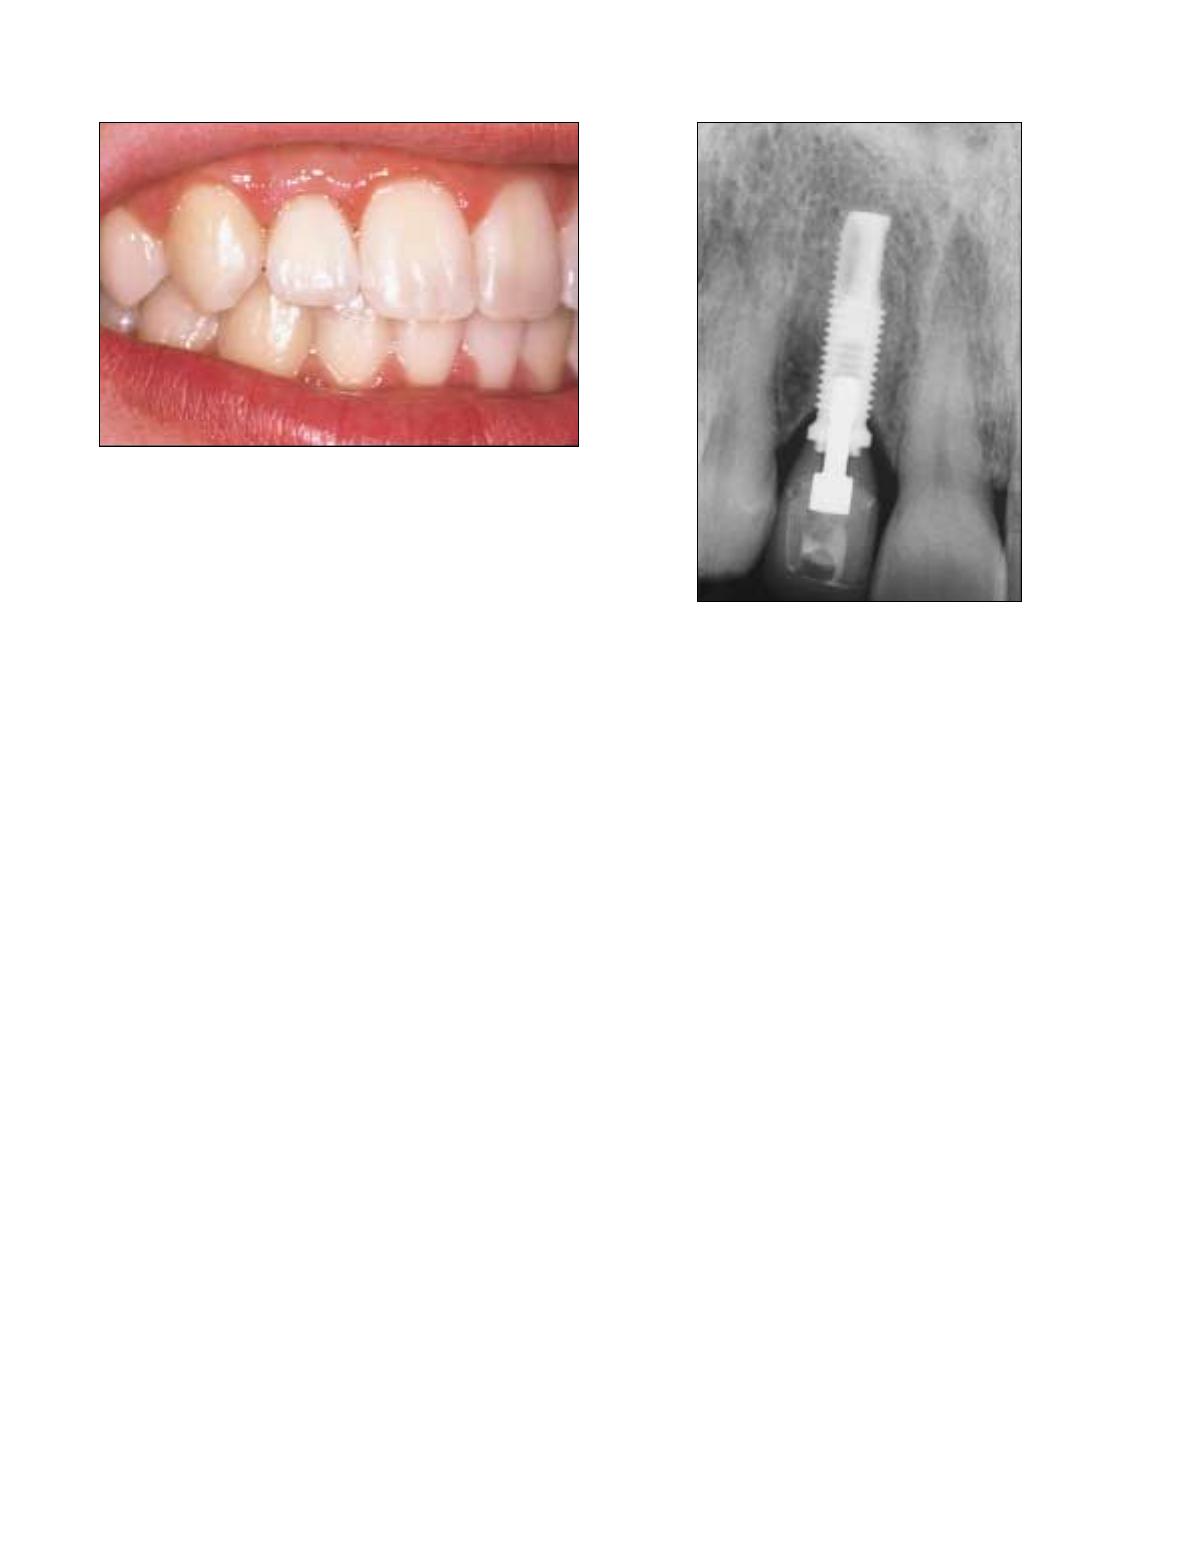

Illustration 5 : L’éruption excessive des dents antérieures inférieures

en raison d’une malocclusion de classe II nuit souvent à l’esthétique

et au bon fonctionnement de la dentition des patients.